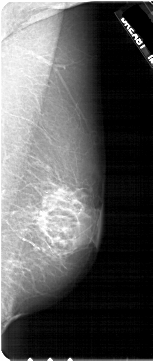

A_1820_1.LEFT_MLO

LEFT_MLO LINES 4996 PIXELS_PER_LINE 2641 BITS_PER_PIXEL 12 RESOLUTION 43.5 OVERLAY

FILE: A_1820_1.LEFT_MLO.OVERLAY

TOTAL_ABNORMALITIES 1

ABNORMALITY 1

LESION_TYPE MASS SHAPE OVAL MARGINS ILL_DEFINED

ASSESSMENT 4

SUBTLETY 4

PATHOLOGY MALIGNANT

TOTAL_OUTLINES 1

BOUNDARY